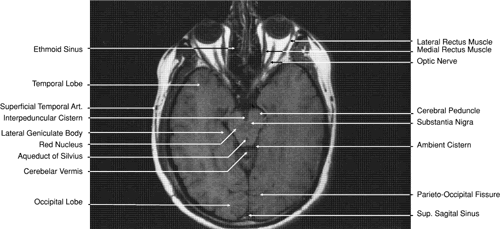

The globe is shown in Figure 12. The orbit and periorbital structures are shown in Figures 13 through 16, and the optic canal is shown in Figures 17 through 26. The cavernous sinus and optic chiasm are shown in Figures 27 and 28, and the posterior visual pathway and cranial nerves are shown in Figures 29 through 33.

Fig. 31. Axial T1-weighted image through the cerebral peduncle at the level of oculomotor nerve.